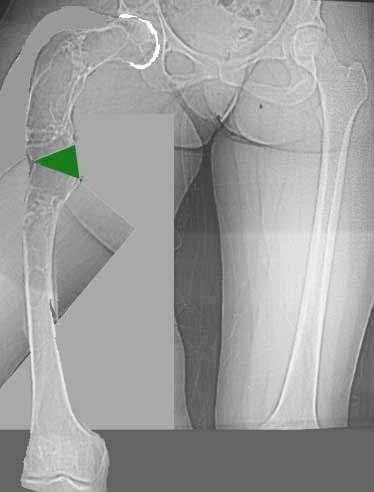

Хотелось бы показать, что получилось в результате.

Операция выполнялась с помощью А.Н.Челнокова. Очень понравилась технология выполнения блокируемого остеосинтеза с использованием спицевого дистрактора, модифицированный гвоздь с латерализованным проксимальным отделом и возможностью многовинтовой фиксации проксимального и дистального участков бедра.